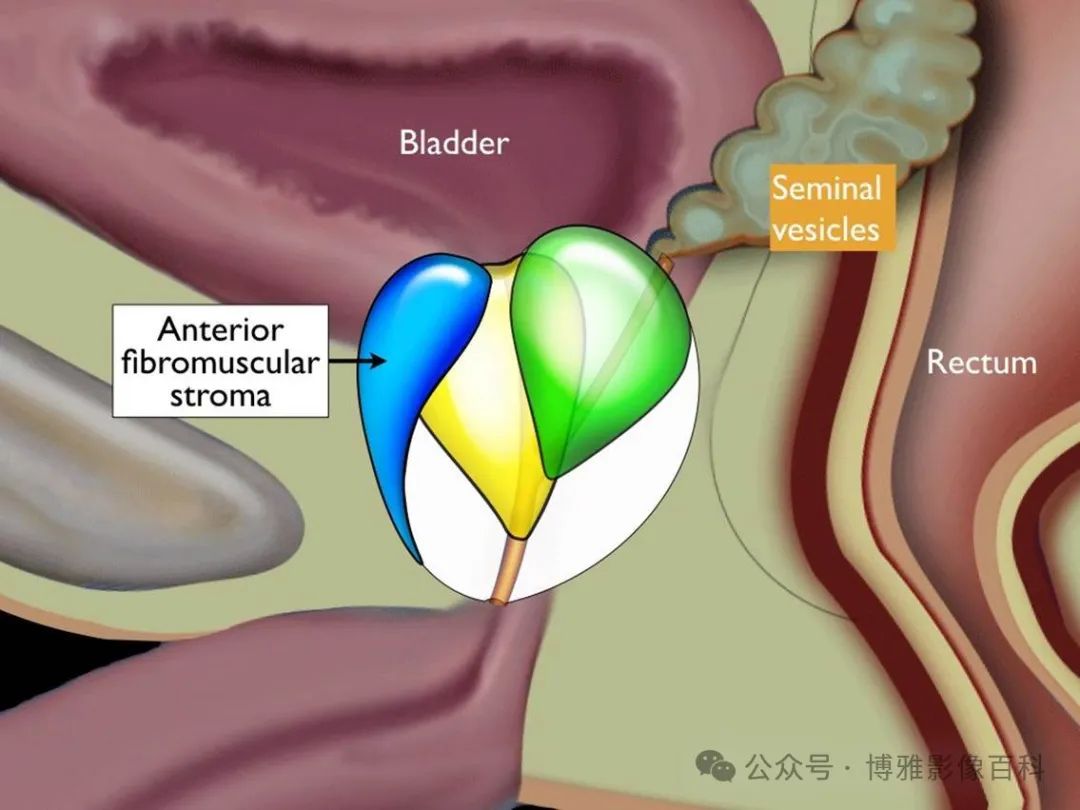

前列腺分区解剖学

25% 的前列腺癌起源于移行带 (TZ)。极少数前列腺癌出现在中央带或前纤维肌基质中。